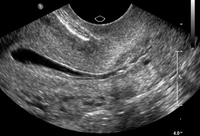

Saline infusion ultrasound with polyp

From the collection of Dr Jared C. Robins